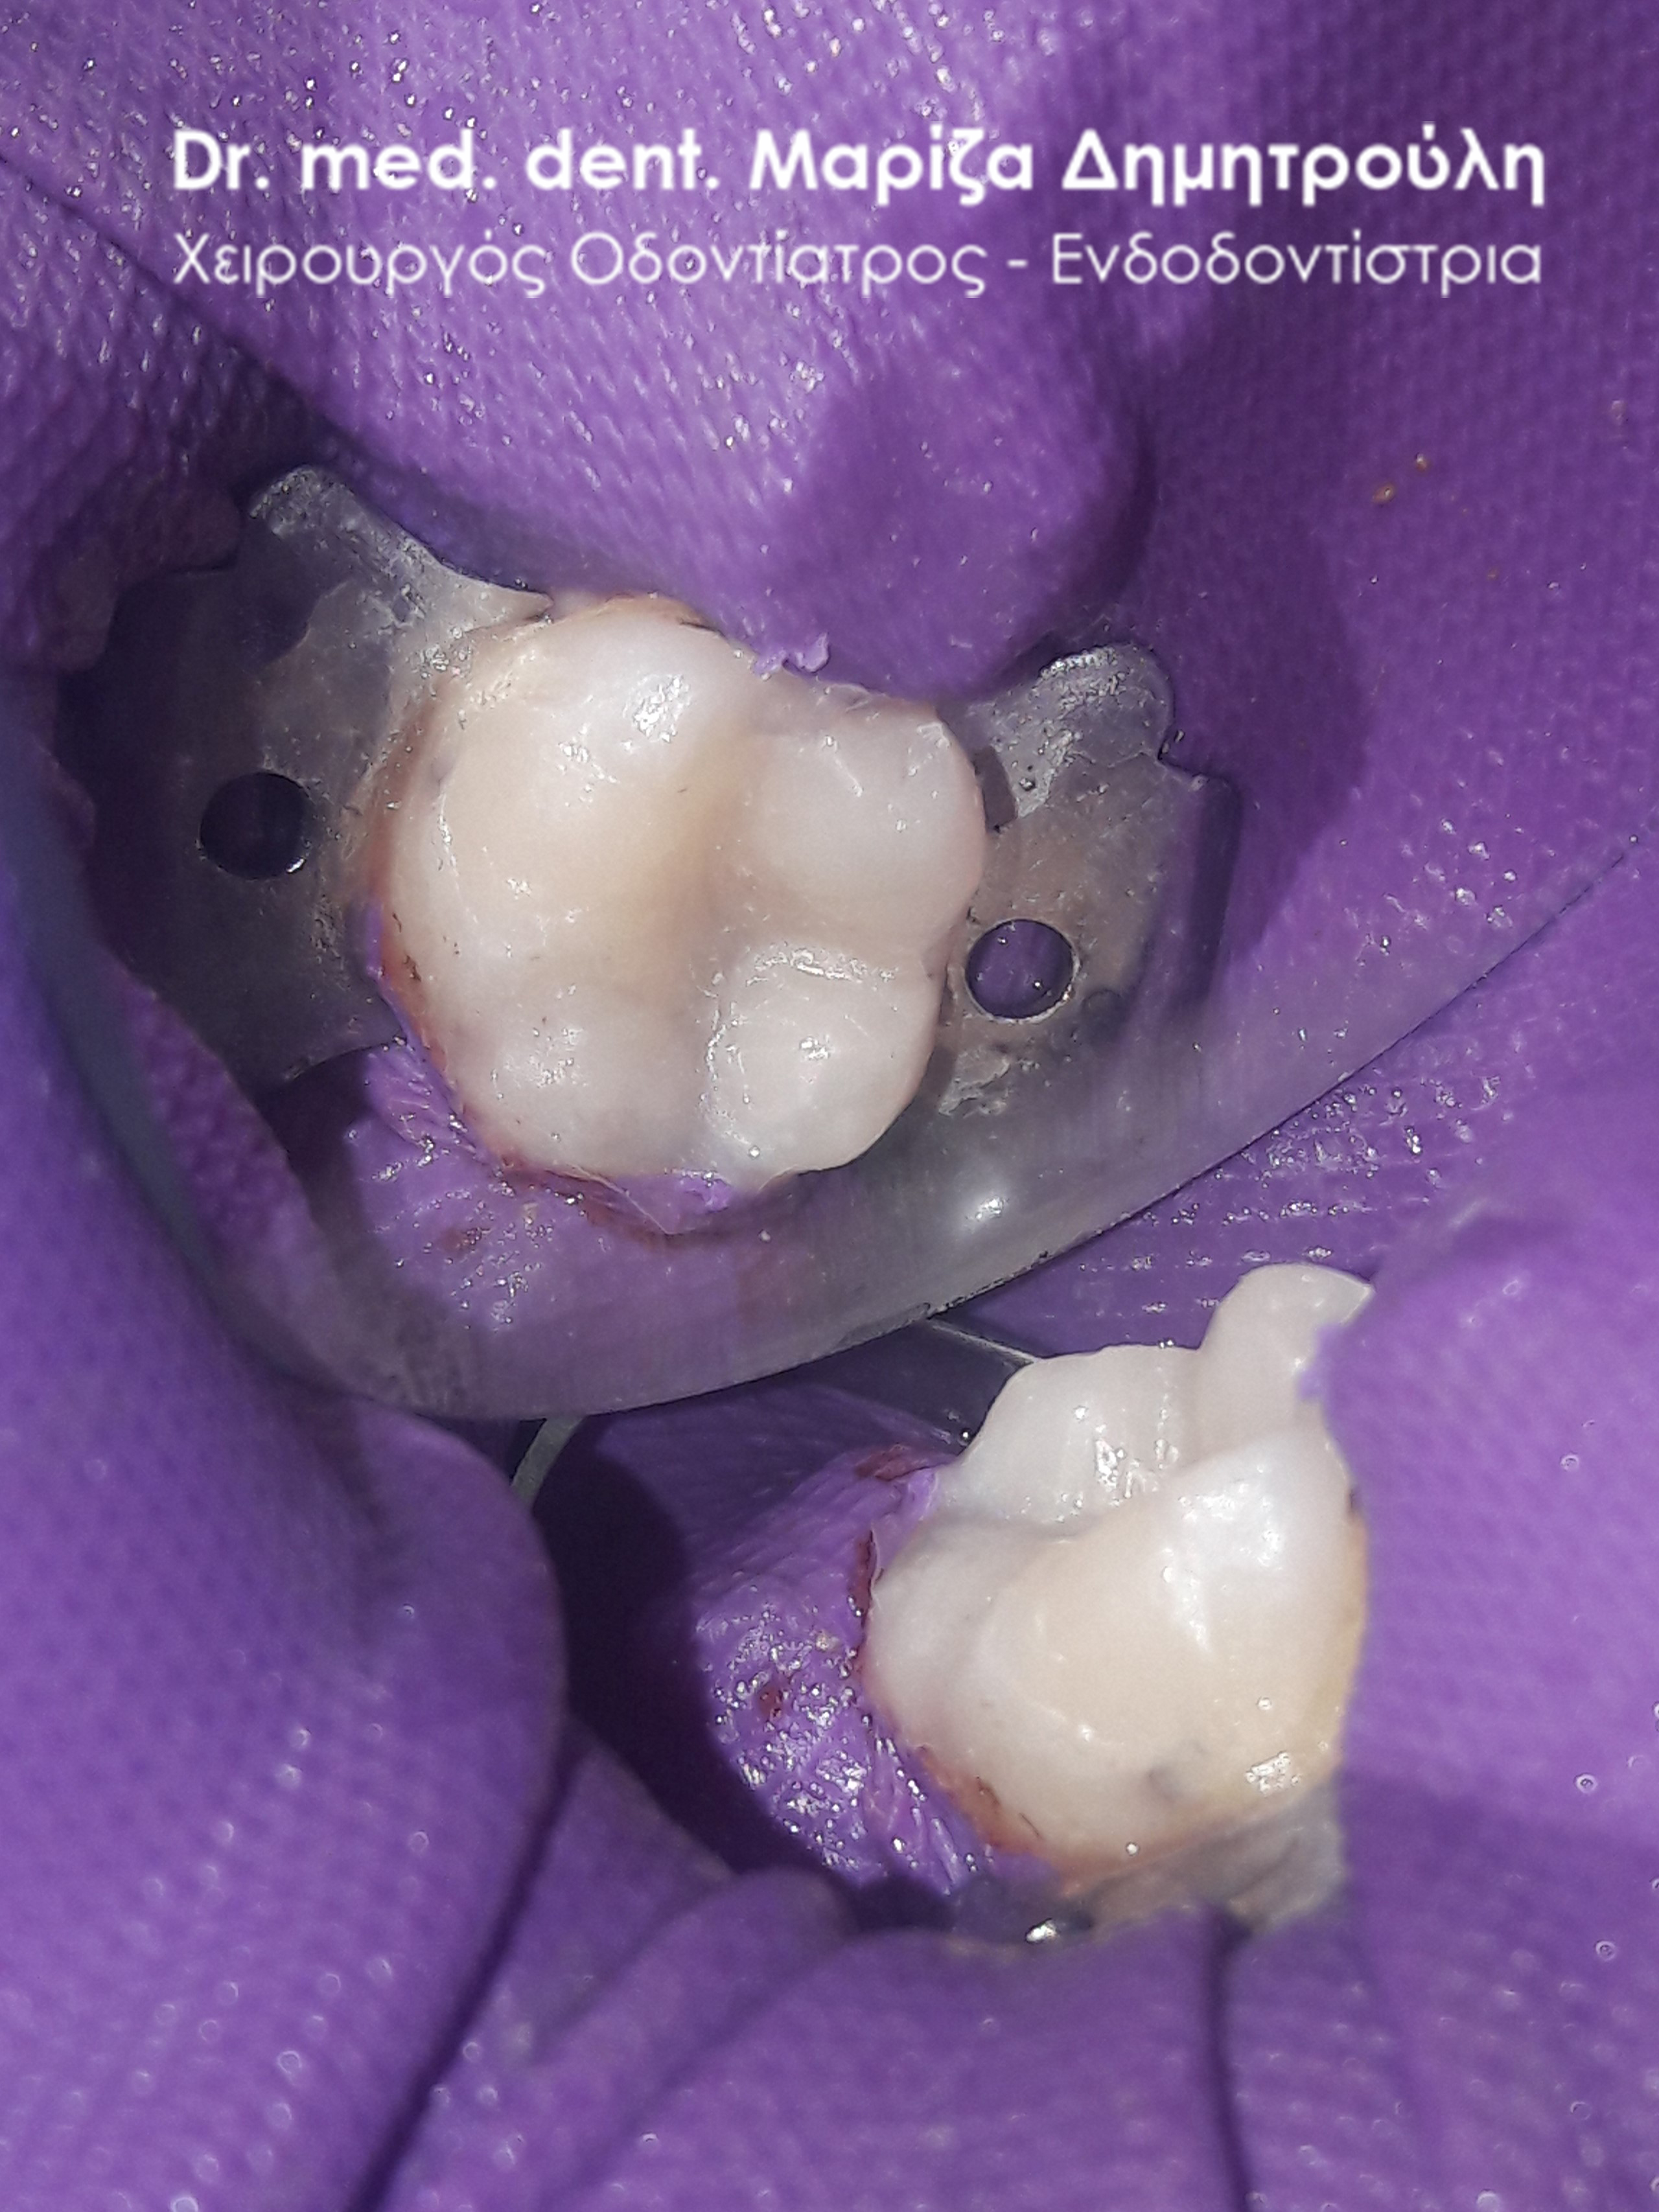

Στο παρόν περιστατικό απουσιάζει η αρχική εικόνα των δύο δοντιών πριν αρχίσει ο εκτροχισμός τους. Διαθέσιμες είναι μόνο η ενδιάμεση εικόνα που παρουσιάζει το εύρος του οδοντικού ελλείμματος στα δύο γομφίους της αριστερής πλευράς της άνω γνάθου και η τελική εικόνα αποκατάστασης των δύο δοντιών.

Η ασθενής αισθανόταν τις τελευταίες μέρες έναν ήπιο πόνο κατά τη μάσηση τροφών. Μετά την κλινική εξέταση του στόματος διαπιστώθηκε η ύπαρξη τερηδονικών κοιλοτήτων στους δύο άνω αριστερούς γομφίους. Αποφασίστηκε με τη συναίνεση της ασθενούς η αντικατάσταση των σφραγισμάτων. Στον πρώτο γομφίο διορθώθηκε μόνο η μισή έκταση του παλιού σφραγίσματος, καθώς κρίθηκε οτι δεν ήταν απαραίτητη η αφαίρεση ολόκληρου του παλιού σφραγίσματος.

ΠΡΙΝ

META